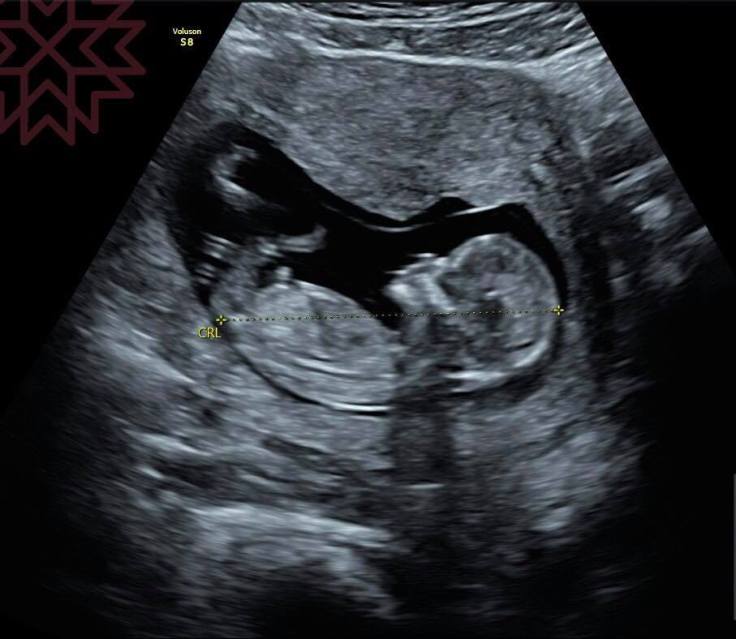

超音波ㄧ放上肚子

恭喜妳

又懷孕嘍~